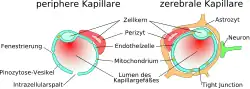

Das Endothel

Die Kapillargefäße werden – wie in den peripheren Blutgefäßen auch – von Endothelzellen gebildet. Das Endothel peripherer Kapillaren hat, für den Austausch von Wasser und darin gelösten oder suspendierten Stoffen zwischen dem Blut und der extrazellulären Flüssigkeit des umliegenden Gewebes, Öffnungen (Fenestrierungen) von ca. 50 nm Durchmesser und Zwischenzellspalten von 0,1 bis 1 µm Weite. Zwischen den Endothelzellen im Gehirn gibt es dagegen keine Fenestrierungen und keine Intrazellularspalten,[7] weshalb man auch von einem kontinuierlichen Endothel spricht.[8] Die dem Innenraum der Kapillare zugewandte (luminale) Membran unterscheidet sich bezüglich der Art der Membranproteine erheblich von der dem Interstitium zugewandten apikalen Seite.

Die Anzahl an pinozytotischen Vesikeln, die eine Endozytose von gelösten Substanzen ermöglichen, ist im Endothel des Gehirns sehr gering.[9][10]

Im Gegensatz dazu ist die Anzahl an Mitochondrien etwa 5- bis 10-mal höher als in den peripheren Kapillaren. Dies ist ein Hinweis auf einen hohen Energiebedarf der Endothelien – unter anderem für aktive Transportprozesse – und eine hohe Stoffwechselaktivität.[3] Die Blut-Hirn-Schranke ist nicht nur eine physikalische, sondern auch eine metabolische beziehungsweise enzymatische Barriere.[11][12][13][14][15] In der Zellmembran der Endothelien befindet sich eine Reihe von Enzymen in deutlich höherer Anzahl als beispielsweise bei den Zellen des Parenchyms. Dazu gehören unter anderem γ-Glutamyltransferase, alkalische Phosphatase und Glucose-6-Phosphatase. Metabolisierende Enzyme wie Catechol-O-Methyltransferase, Monoaminooxidase oder Cytochrom P450 sind ebenfalls in einer relativ hohen Konzentration in den Endothelien aktiv.[16][17][18] Auf diese Weise werden viele Substanzen bereits vor oder während ihres intrazellulären Transportes metabolisiert.[11] Die Endothelzellen sind mit 0,3 bis 0,5 µm äußerst dünn. Enterozyten, die Epithelzellen des Darmes, sind im Vergleich dazu mit 17 bis 30 µm erheblich dicker.[19] Das Verhältnis von Cholesterin zu Phospholipiden liegt, wie bei anderen Endothelzellen auch, bei 0,7.[20] Reine Diffusionsprozesse durch die Zellmembran sind daher über die Blut-Hirn-Schranke ähnlich schnell wie bei anderen Endothelzellen.[21] Die Endothelzellen weisen auf ihrer Zellmembran für die Regulation des Wasserhaushaltes des Gehirnes eine Vielzahl von Aquaporinen auf. Diese Kanäle ermöglichen Wassermolekülen die freie Diffusion sowohl in Richtung Gehirn als auch zum Blut.[22]

Die Perizyten

Perizyten, vor allem in der älteren Literatur nach ihrem Entdecker Charles Marie Benjamin Rouget (1824–1904) als Rouget-Zellen[32] bezeichnet, sind ein wichtiger Bestandteil der Blut-Hirn-Schranke.[33] Drei wesentliche Eigenschaften stehen dabei im Vordergrund: ihre Fähigkeit zur Kontraktion, die Regulierung der Endothelien und ihre Makrophagen-Aktivität.[34]

Etwa 20 % der äußeren Endotheloberfläche der zerebralen Kapillaren ist von den relativ kleinen, oval geformten Perizyten bedeckt und jede zweite bis vierte Endothelzelle ist mit einem Perizyten verbunden.[6] Bevorzugt befinden sich die Perizyten dabei an der Kontaktstelle zweier Endothelzellen.[35][36] Perizyten finden sich auf nahezu allen Arteriolen, Venolen und Kapillaren – nicht nur im zerebralen Endothel. Der Bedeckungsgrad des Endothels mit Perizyten korreliert unmittelbar mit der Undurchlässigkeit der Tight Junctions. Bei fenestrierten Kapillaren, beispielsweise in der Skelettmuskulatur, liegt das Verhältnis von Endothelien zu Perizyten bei 100:1.[37][38]

Die Astrozyten

Astrozyten sind sternförmig verzweigte, im Vergleich zu den Perizyten deutlich größere Zellen aus der Familie der Makroglia. Sie werden dem Zentralen Nervensystem zugerechnet und sind nach der Geburt noch teilungsfähig. Bei höheren Wirbeltieren haben sie keine direkte Schrankenfunktion, auch wenn sie die Kapillargefäße im Gehirn zu etwa 99 % mit ihren Endfüßchen bedecken.[6][53] Sie stehen allerdings in unmittelbarer Wechselwirkung mit den Endothelien.[54] Astrozyten induzieren in den Endothelien der zerebralen Blutgefäße die Funktion der Blut-Hirn-Schranke. Dies wurde durch Transplantationsversuche nachgewiesen. Zerebrale Blutgefäße, die in periphere Organe verpflanzt wurden, verhielten sich wie die dort vorhandenen „normalen“ Kapillaren und bildeten beispielsweise Fenestrierungen aus. Im umgekehrten Versuch nahmen periphere Kapillaren, die in das Zentralnervensystem verpflanzt wurden, den dortigen Phänotyp mit Tight Junctions an.[1][55] Auch in In-vitro-Versuchen zeigt sich der Einfluss der Astrozyten auf die Phänotypausprägung der Endothelien. In Co-Kulturen aus Astrozyten und Endothelzellen weisen die Endothelien eine höhere Dichtigkeit auf als in reinen Endothelkulturen.[56]